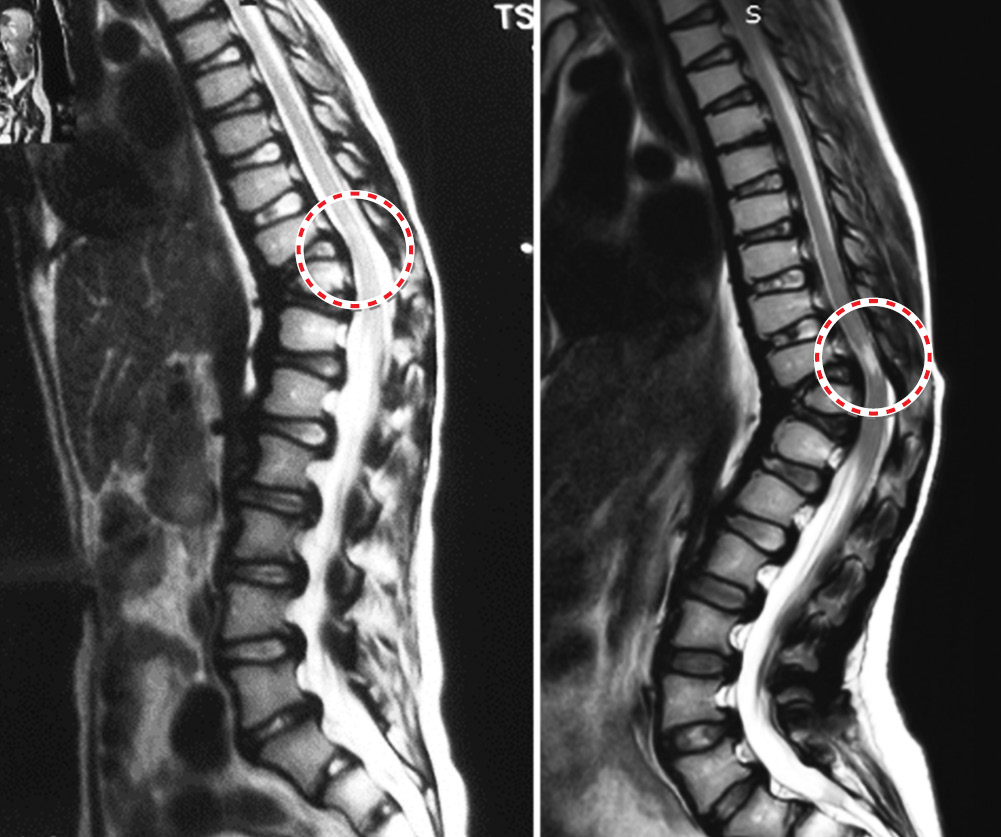

В периоперационном периоде у данной пациентки выявлено наличие кифотической деформации грудопоясничного отдела позвоночника (34°) с очагом миелопатии на вершине кифоза (уровень Th11). Рекомендовано динамическое наблюдение и плановое хирургическое лечение. Однако от предложенного лечения пациентка отказалась. Через 4 года после первой операции стала отмечать трудности при ходьбе, слабость в нижних конечностях, нарушение баланса туловища, выраженные боли в области грудопоясничного отдела позвоночника (8 баллов по визуально аналоговой шкале). На рентгенограммах угол локального кифоза по Сobb составил 50°. Согласно данным МРТ, очаг миелоишемии увеличился (рис. 4).

Рис. 4. Магнитно-резонансная томограмма грудопоясничного отдела позвоночника, отмечается очаг миелопатии на уровне позвонка Th11